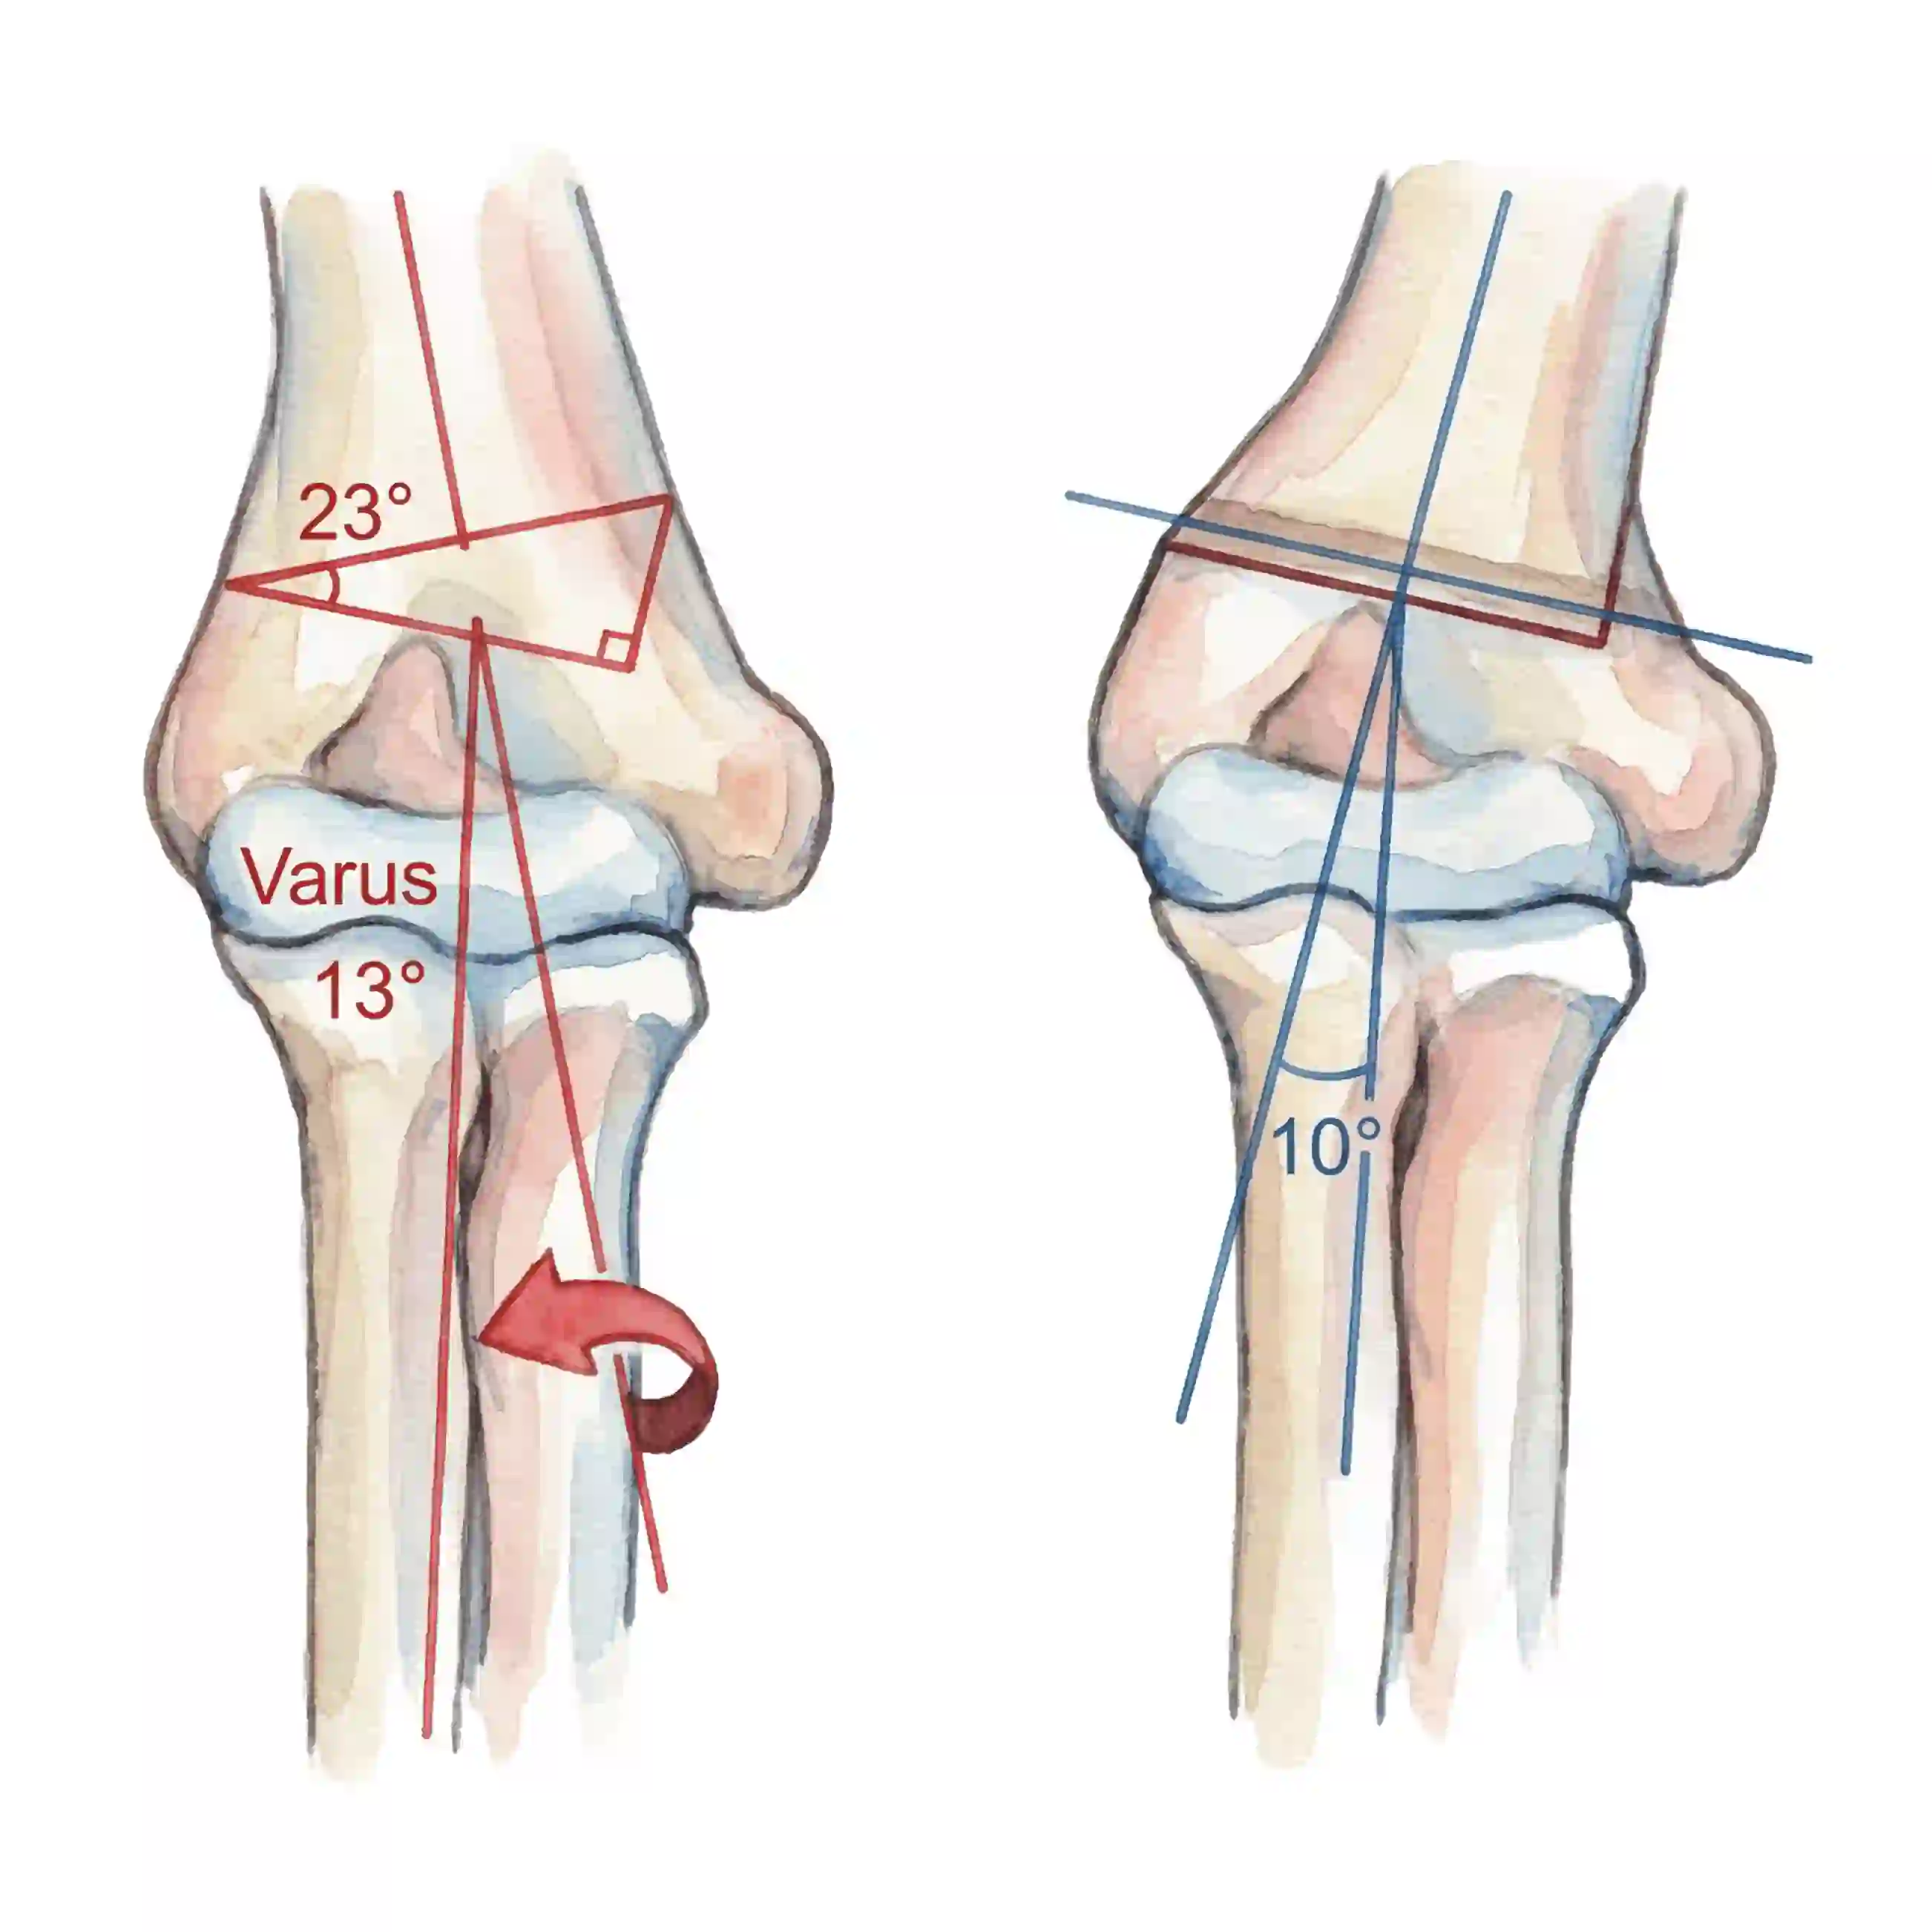

Carrying Angle Lost

Normal outward angle (5-15°) reverse हो जाता है। Inward bend हो जाता।

Carrying Angle Lost

Normal outward angle (5-15°) reversed. Arm bends inward instead of outward.